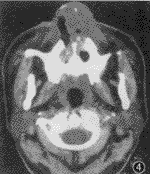

图4 鼻腔外周T细胞性淋巴瘤,右鼻前庭肿物,累及鼻翼,并见鼻翼坏死、溃烂

2.病灶形态及密度:8例病灶以增殖为主,呈肿块状(图2,3),其中6例合并浸润,1例鼻翼明显溃烂(图4)。3例以浸润为主,表现类似黏膜增厚或鼻翼增厚(图5),其中2例弥漫浸润(图6)。CT值23.1~59.8 HU,增强后最高达88.6 HU。肿块密度相对均匀,浸润型病灶则呈混杂密度。